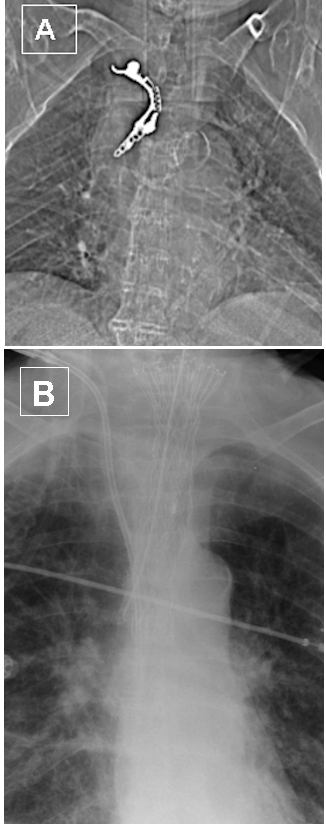

Durch die Diagnostik müssen die wichtigsten Kriterien für die Therapieentscheidung herausgearbeitet werden. Wichtig dabei ist die Lokalisation und Ausdehnung der Leckage [26]. Es sollte geklärt werden, ob ein Anschluss an Pleura- oder Bauchhöhle vorliegt. Auch die Ausdehnung der mediastinalen Infektion ist von höchster prognostischer Bedeutung. Durchblutungsverhältnisse des Ösophagus im Bereich der Perforationsstelle sollten bei der Therapiegestaltung ebenfalls berücksichtigt werden. Die Röntgen-Thorax- und Abdomen-Leeraufnahme sind nur zur Klärung der Frage nach mediastinaler oder pleuraler Luft oder freier Luft im Abdomen ausreichend. Genauer sind die Kontrastmittel gestützte Spiral-Computertomografie und die Endoskopie [27]. Abbildung 2A [Abb. 2] zeigt eine verschluckte Zahnprothese mit Ösophagusperforation, Abbildung 2B [Abb. 2] den Zustand nach Stentimplantation.

Abbildung 2: A: Zahnprothese im Ösophagus mit Perforation. B: Stentimplantation nach Bergung der Prothese.